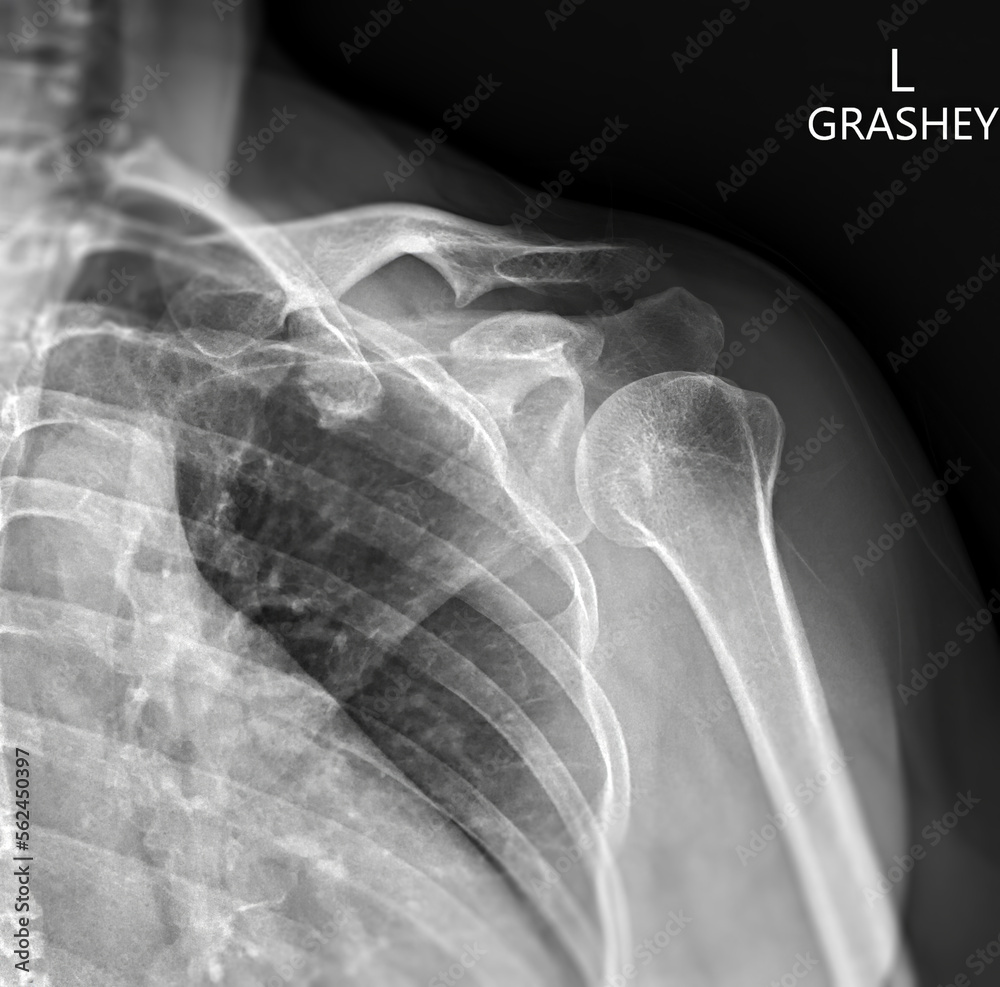

Рентгеновские снимки саркомы плечевого сустава